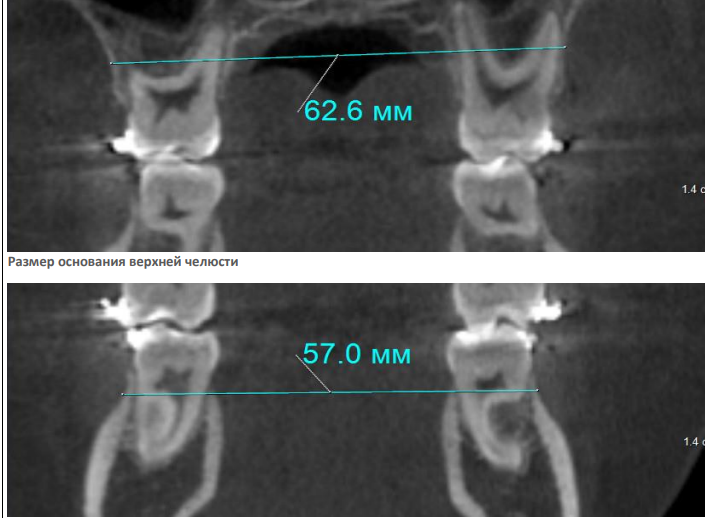

На КЛКТ определяются зачатки вторых и третьих моляров на верхней и нижней челюсти, степень формирования которых соответствует возрасту и полу. Невысокое положение клыков с увеличенной мезиальной ангуляцией.

На ТРГ головы в боковой проекции - ретроположение верхней и нижней челюсти в сагиттальном направлении без нарушения размеров апикальных базисов и их взаиморасположения. Тип роста – нейтральный. Дентоальвеолярный анализ характеризует изменение инклинации резцов на верхней и нижней челюсти с незначительным дентоальвеолярным удлинением. На нижней челюсти в области боковой группы зубов определяется зубоальвеолярное укорочение, что характеризует формирование глубокой кривой Spee на данном этапе формирования прикуса постоянных зубов. (рис.3.)

Рис. 3. КЛКТ и ТРГ головы в боковой проекции пациента А. до лечения.

Рис.10. КТ челюстей, характеризующая нормальные параметры апикальных базисов челюстей в трансверзальном направлении с правильным расположением по инклинации моляров верхней и нижней челюсти.